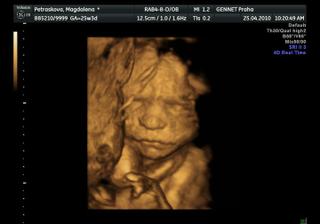

25.4.2010-razíme na 4D utz tak snad se nám princezna ukáže v plné kráse =0*

no vypadaj fakt velký =D